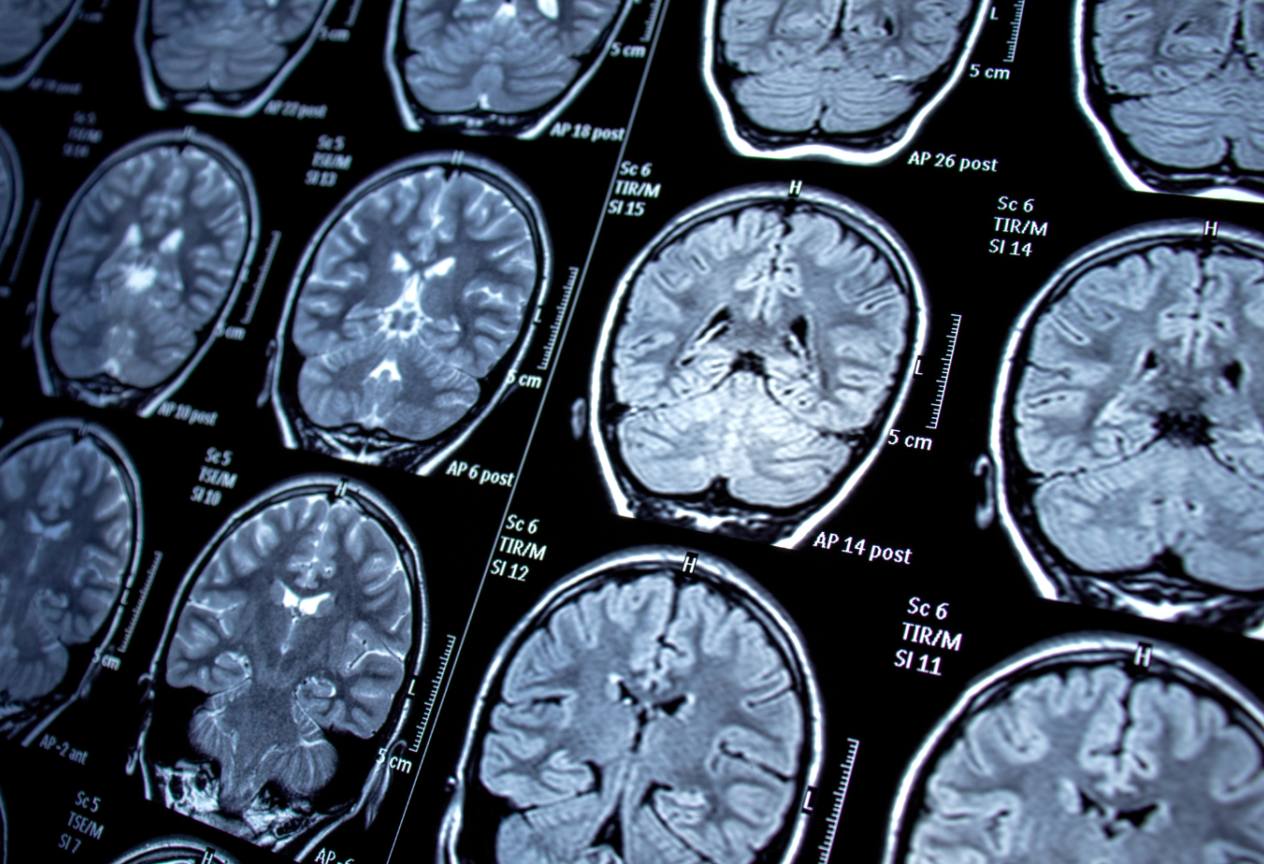

Diagnose einer Epilepsie Anamnese, EEG & MRT Nutmeg Epilepsy The results indicate that nutmeg oil may be effective against grand mal and partial seizures, as it prevents seizure spread in a set of. Seizures associated with intentional severe nutmeg intoxication. In conclusion, nutmeg extract might be regarded as a useful supplementary agent in epilepsy treatment through its attenuation of neuronal. Research has found that several diets, such as the. Nutmeg Epilepsy.